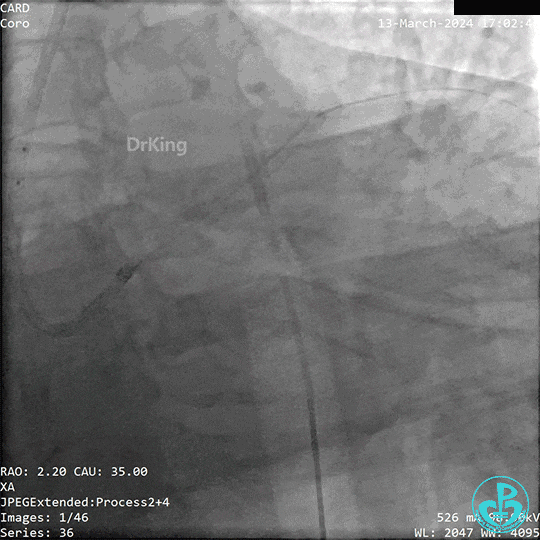

2.手艺界说

血管内攻击波碎石术,即震波球囊手艺,是一种治疗中重度钙化病变的新手艺。其使用体外装备将电能转达到发射器上,通过发射器爆发“声波压力波”,即将球囊内液体气化,借助气化的液体对血管内膜、中膜的钙化举行隔空“敲打”,同时对血管组织没有或险些没有影响,增添血管顺应性,从而抵达治疗目的。